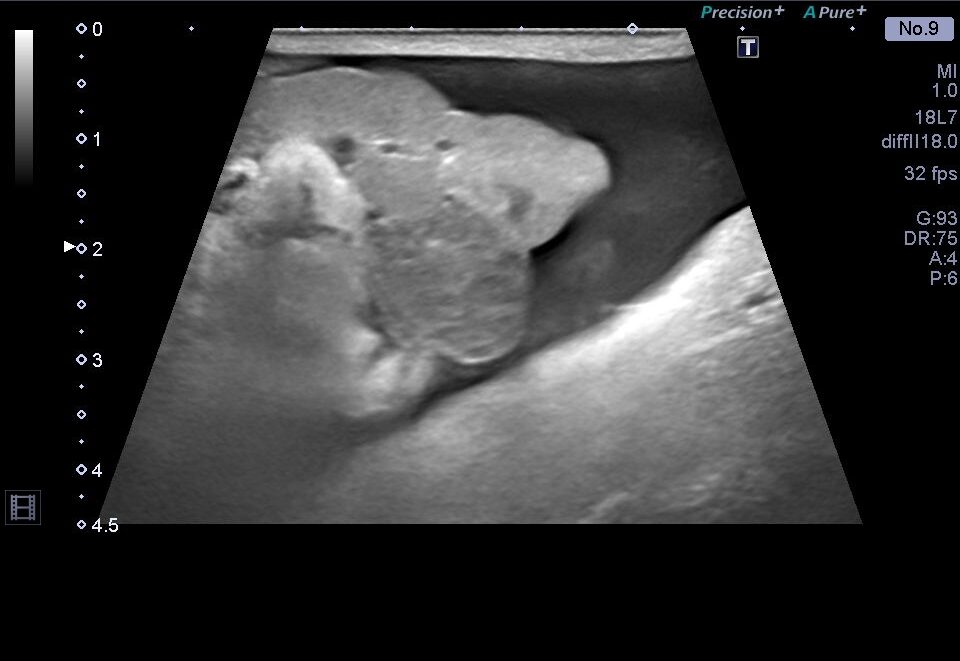

腹部の超音波検査では、肺高血圧症が原因と思われる腹水の貯留を認めたため、腹水の抜去を行いました。